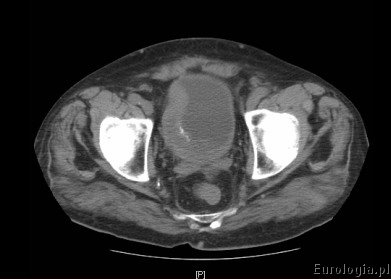

Fot. Guz pęcherza moczowego - obraz w tomografii komputerowej.